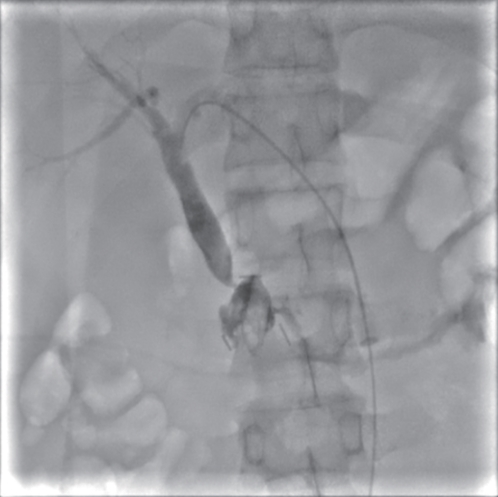

Successful treatment of biliary fistula after Beger surgery by oral choledochoscopy-assisted percutaneous-endoscopic rendezvous technique: A case report

Yuxin WANG, Weigang GU, Zheng JIN, Xiaofeng ZHANG

2025, 41(2): 333-336. DOI: 10.12449/JCH250220

Abstract(927) HTML (261) PDF (4794KB)(52)

Abstract:

Duodenum-preserving pancreatic head resection, also known as Beger surgery, has a high incidence rate of bile duct injury after surgery, while the treatment modality for bile duct injury depends on the severity of the injury, and endoscopic therapy is often challenging in case of severe bile duct injury. Recently a patient with biliary fistula after Beger surgery was admitted to Affiliated Hangzhou First People’s Hospital, Westlake University, and successful diagnosis and treatment were achieved through oral choledochoscopy-assisted percutaneous-endoscopic rendezvous technique.